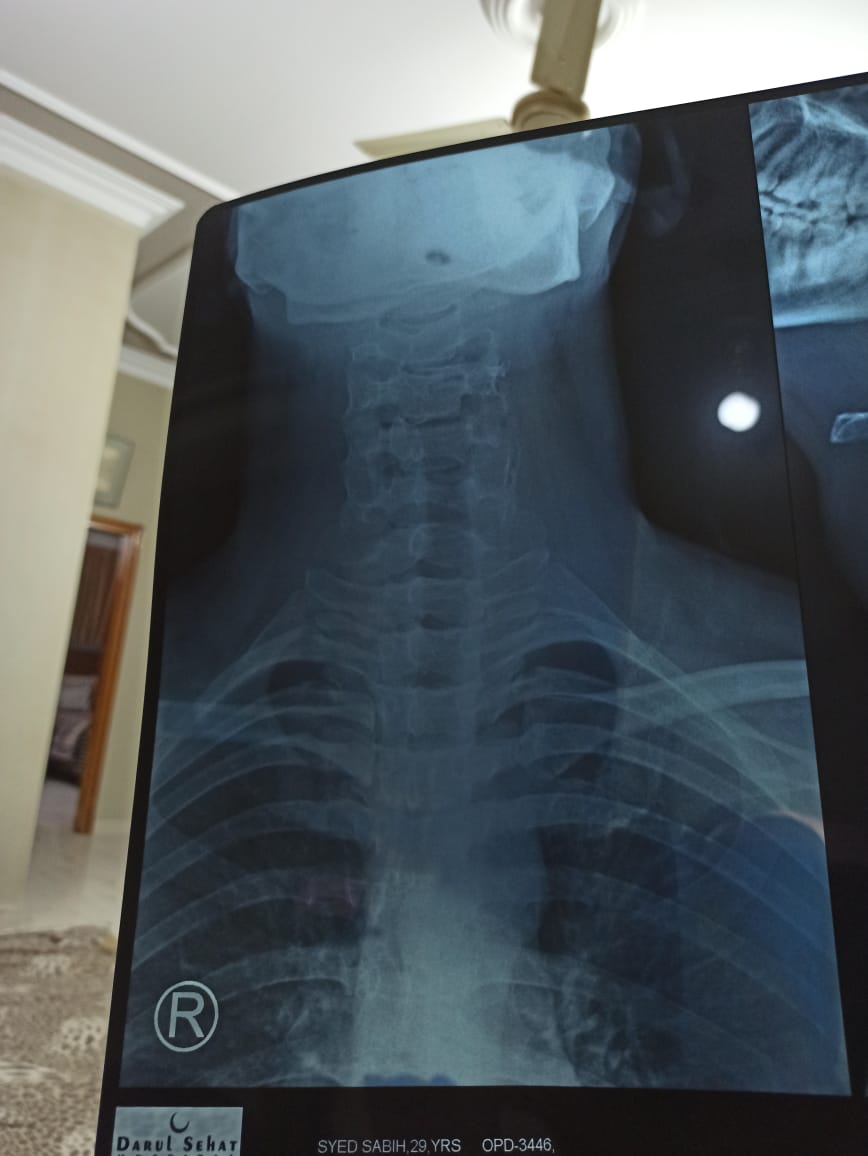

I have been stiff neck problems for quite sometime now where I wake up with a stiff neck which leads to headaches. I work in IT and have a desk job 9 hours a day. I have recently had my neck X-ray done on the advice of my doctor. I seek help as I will not be able to visit my doctor due to work. Doc works in the weekdays and so do I. I need someone qualified to take a look at my x-ray and tell me if there is anything wrong. I would be grateful. Bless you!

Attach Photo here: